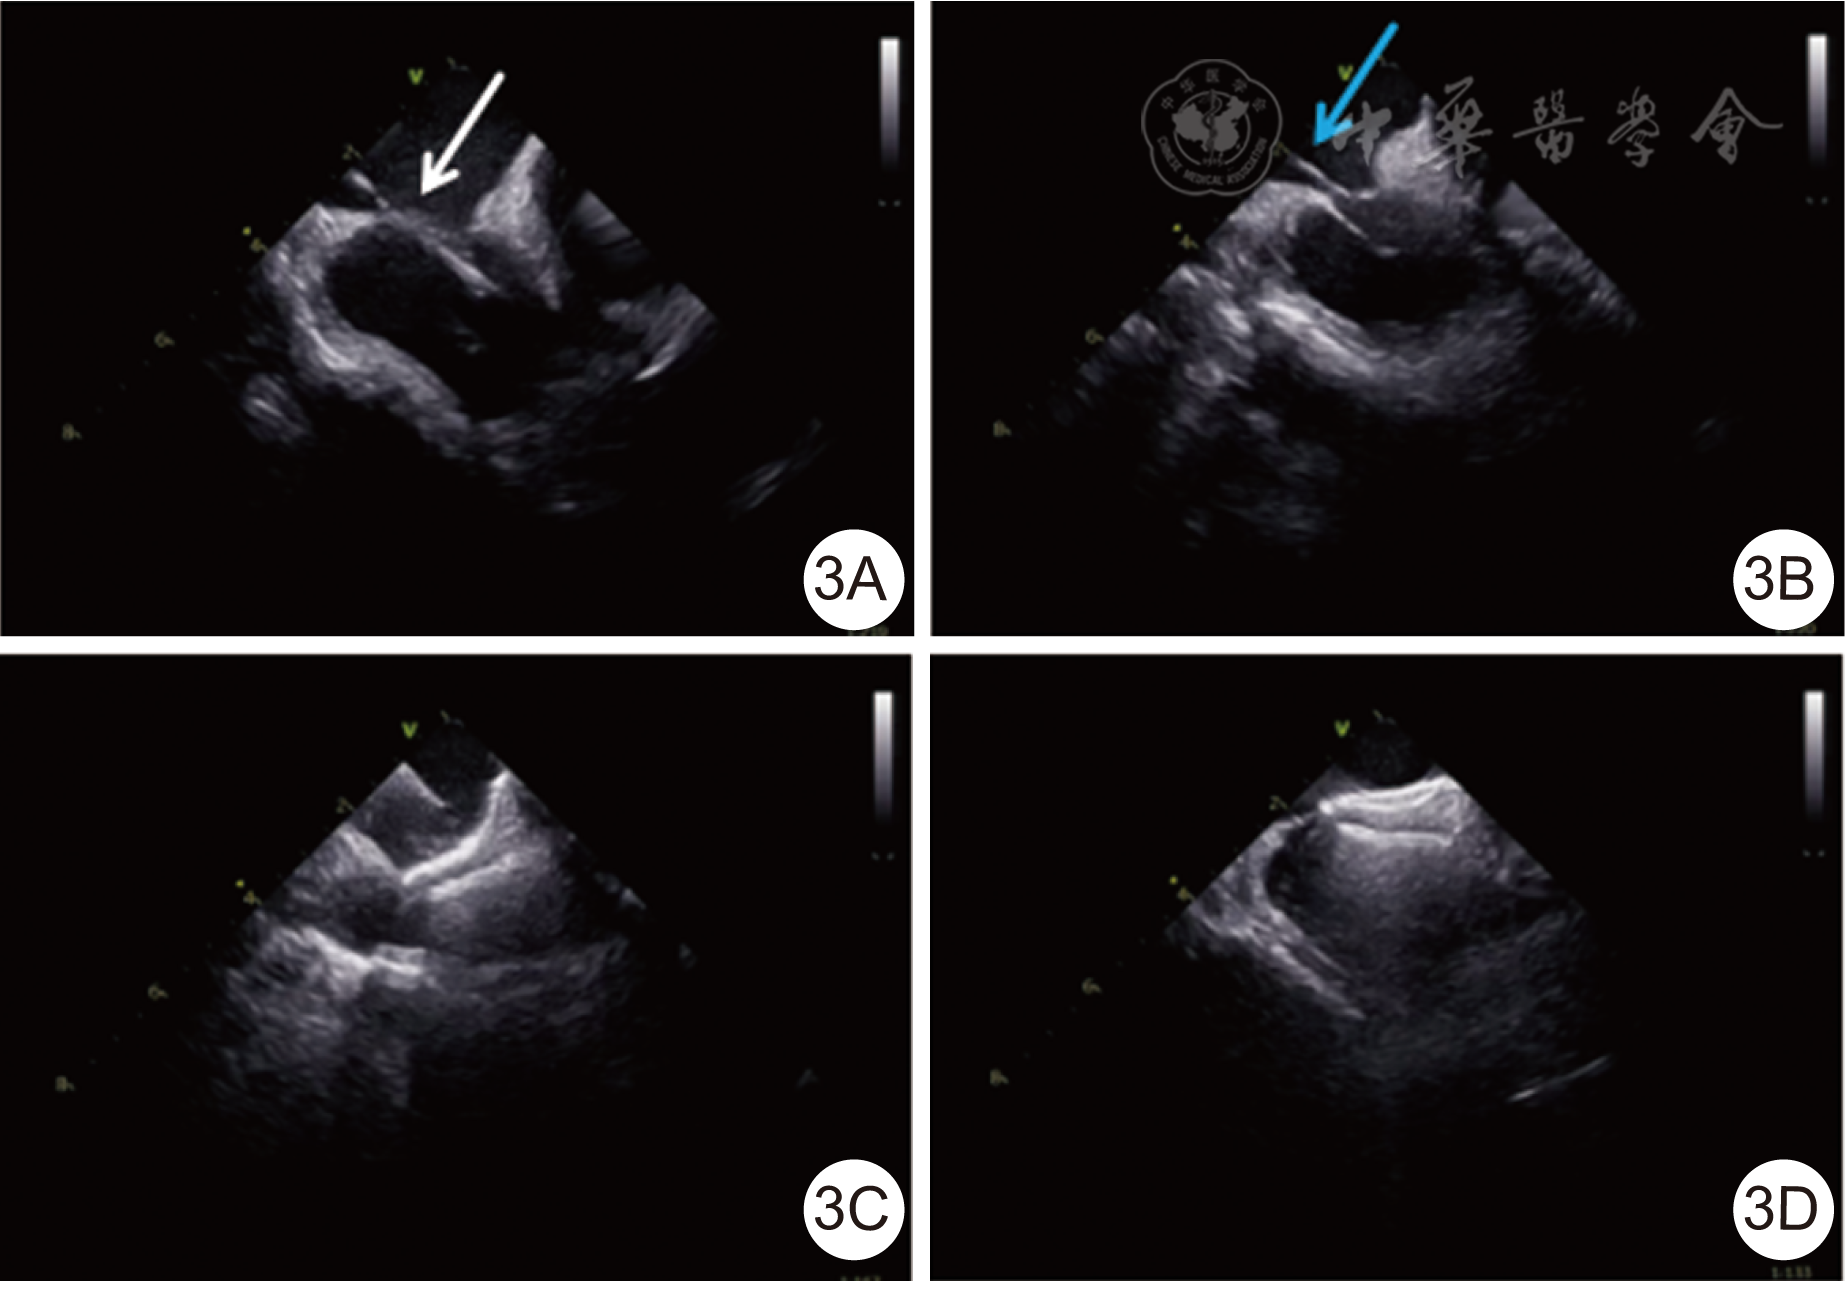

图3 心腔内超声心动图指导卵圆孔未闭(PFO)封堵流程[3A为钢丝跨过PFO(白色箭头);3B为输送鞘通过PFO(蓝色箭头);3C为封堵器前后伞展开;3D为释放封堵器]